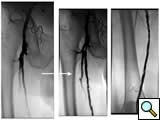

Case 3: An 81-year-old male with rest pain. The patient underwent angiography via an antegrade approach, which revealed extensive

![]() |

| Figure 3A |

| Figure 3B |

| Figure 3C |

calcific lesions of the superficial femoral artery (Figure 3A) and a lesion in the tibio-peroneal trunk (Figure 3B). The SFA lesions were debulked with a laser and the patency restored with Viabahn stents (Figure 3C). The tibio-peroneal represented the sole run off and was left as we were worried about creating a disaster if the lesion ruptured or dissected. ABI increase from 0.19 pre-procedure to 0.55 post and the patient is now able to ambulate with manageable claudication. Options to treat the more distal lesion could involve using a distal protection device and coronary balloons and/or stents.